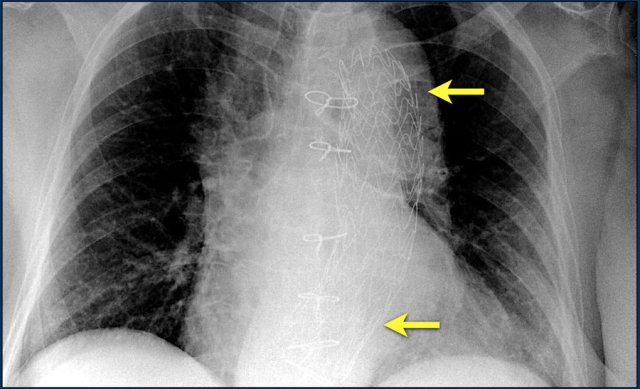

The image is taken immediately after placement of an ICD.

There is a small pneumothorax (arrow).

This is the most common complication.